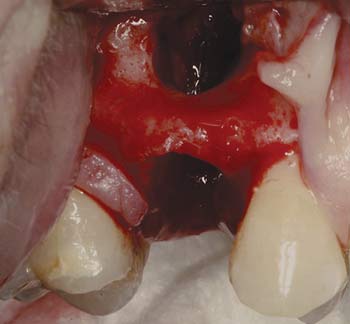

MinerOss Blend cases

grafting for implant placement

MinerOss Blend case 1

MinerOss Blend case provided by Dr. Bach Le